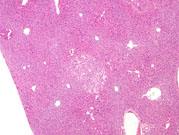

Fatty change, mild. The circular clear spaces represent areas previously occupied by fat in this mouse on a choline deficient diet. The fat is dissolved out by xylene during processing of the tissue.